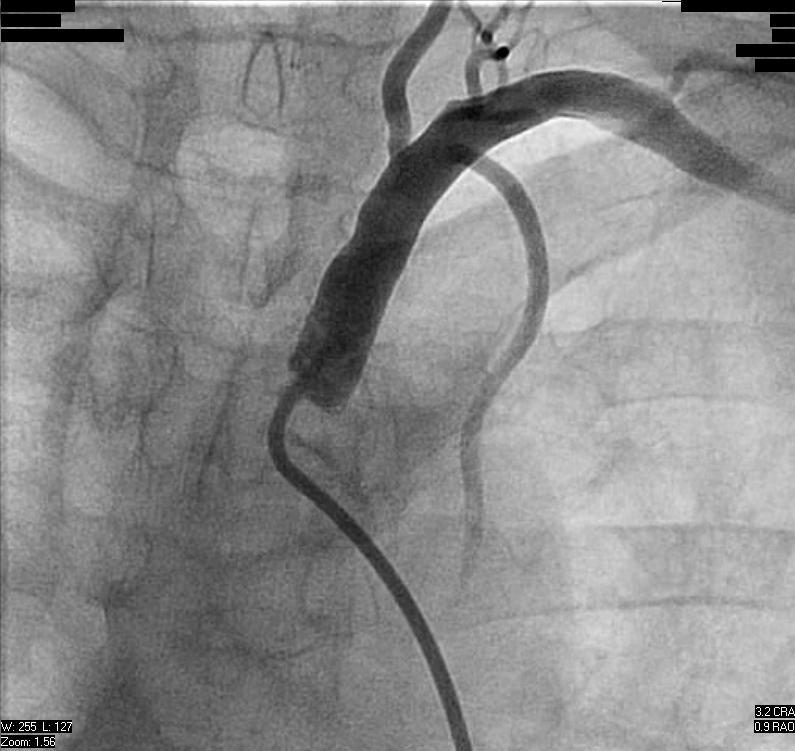

Successful Subclavian Intervention – Pictorial

For illustrative purposes, Figures 4-6 show successful stent placement in a patient with left subclavian stenosis.